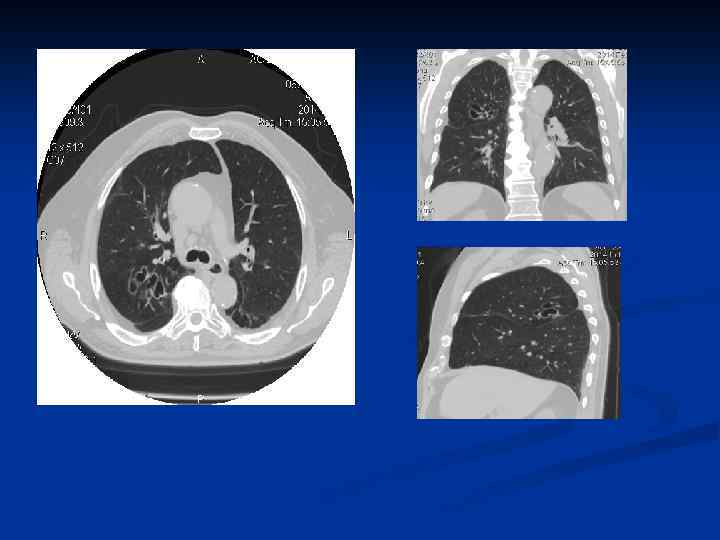

n КТ обладает способностью выявлять все структурные изменения легочной паренхимы, перестройку сосудистобронхиальной архитектоники, уплотнение интралобулярных и перилобулярных перегородок, перибронхиальный и периваскулярный фиброз, буллезные вздутия и эмфизему. На компьютерных томограммах лучше выявляется картина перестройки легочной ткани по типу сотового легкого, чаще всего развивающегося в периферических субплевральных отделах.

n n n Бронх считается расширенным, если его внутренний просвет значительно превышает диаметр сопутствующей ему парной ветви легочной артерии. Бpонхоэктазы выявляются в виде полостей, заполненных воздухом или секpетом. По денситометрической характеристике бронхоэктазы могут быть трех типов: 1) полости, содержащие воздух, выглядят в виде кольцевидных или щелевидных теней мягкотканной плотности, окружающих просветления высокой прозрачности; 2) полости, содержащие мокроту, могут иметь вид кольцевидных или щелевидных образований мягкотканной плотности, содержимое которых приближается к плотности воды; 3) заполняющая бронхоэктазы густая, вязкая мокрота может давать очаговые тени, близкие по плотности к оружающей фиброзной ткани. В этих случаях приходится ориентироваться на общую структуру пораженного участка легкого и архитектонику бронхиального дерева.